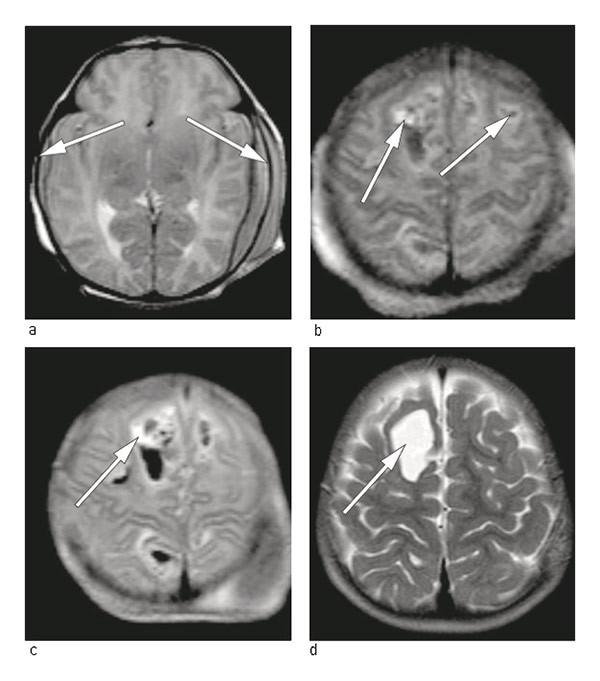

Figure 1  MRI of head, T2 image with 1.5 Tesla scanner. The images during the first day of life show a) fresh subdural…

Figure 1 MRI of head, T2 image with 1.5 Tesla scanner. The images during the first day of life show a) fresh subdural haematomas (arrows) and b) mixture of fresh and 3 – 4 day-old intracerebral haematomas (arrows). c) Control after 24 hours shows an increase in the size of one intracerebral haematoma (arrow). d) After 15 months a cavity remains frontally after the largest intracerebral haematoma (arrow)

Two healthy, unrelated adults had their first baby after an uncomplicated pregnancy. The birth occurred at gestational age 39 weeks and two days. The child was delivered by acute caesarean section because of occiput posterior, protracted delivery and weak contractions. The baby was limp and pale at birth, weighed 2 740 g and had Apgar scores of 2, 6 and 7 after one, five and ten minutes, respectively. Because of respiratory problems she was ventilated with mask and bag for the first three minutes, then with Neopuff (mask CPAP) for 15 minutes. Multiple petechiae and haematomas on the head were observed immediately after birth. Haematological tests revealed severe thrombocytopenia – 9 · 109 cells/L (145 – 390 · 10⁹ cells/L). Irradiated platelet concentrate from four random donors (15 ml/kg), intravenous injection of 0.8 g/kg immunoglobulin (IVIg) and orally vitamin K were administered. Cerebral ultrasound revealed parenchymal haemorrhage medially in the parietal cortex bilaterally. Closer examination in the form of an MRI of the head revealed bilateral cortical and epidural haemorrhages (Fig. 1). These were interpreted as being fresh. The neurosurgeon recommended further observation and conservative treatment.

After discharge the child was monitored by means of blood tests, first monthly and then every second month for six months. The platelet count remained consistently within the normal range (326 – 402 · 10⁹ cells/L). A cerebral MRI was repeated at the ages of one and 15 months (Fig. 1). The child has later shown normal psychomotoric development and is now a healthy five year-old.

The birth of the first child up until surgical delivery took place was protracted. The intracranial haemorrhage was fresh at the time of birth (Fig. 1). One may wonder whether this could have been avoided if the maternal platelet type and antibody level during pregnancy had been known, and a caesarean section had been performed 2 – 3 weeks before term, with compatible platelets available for the child.